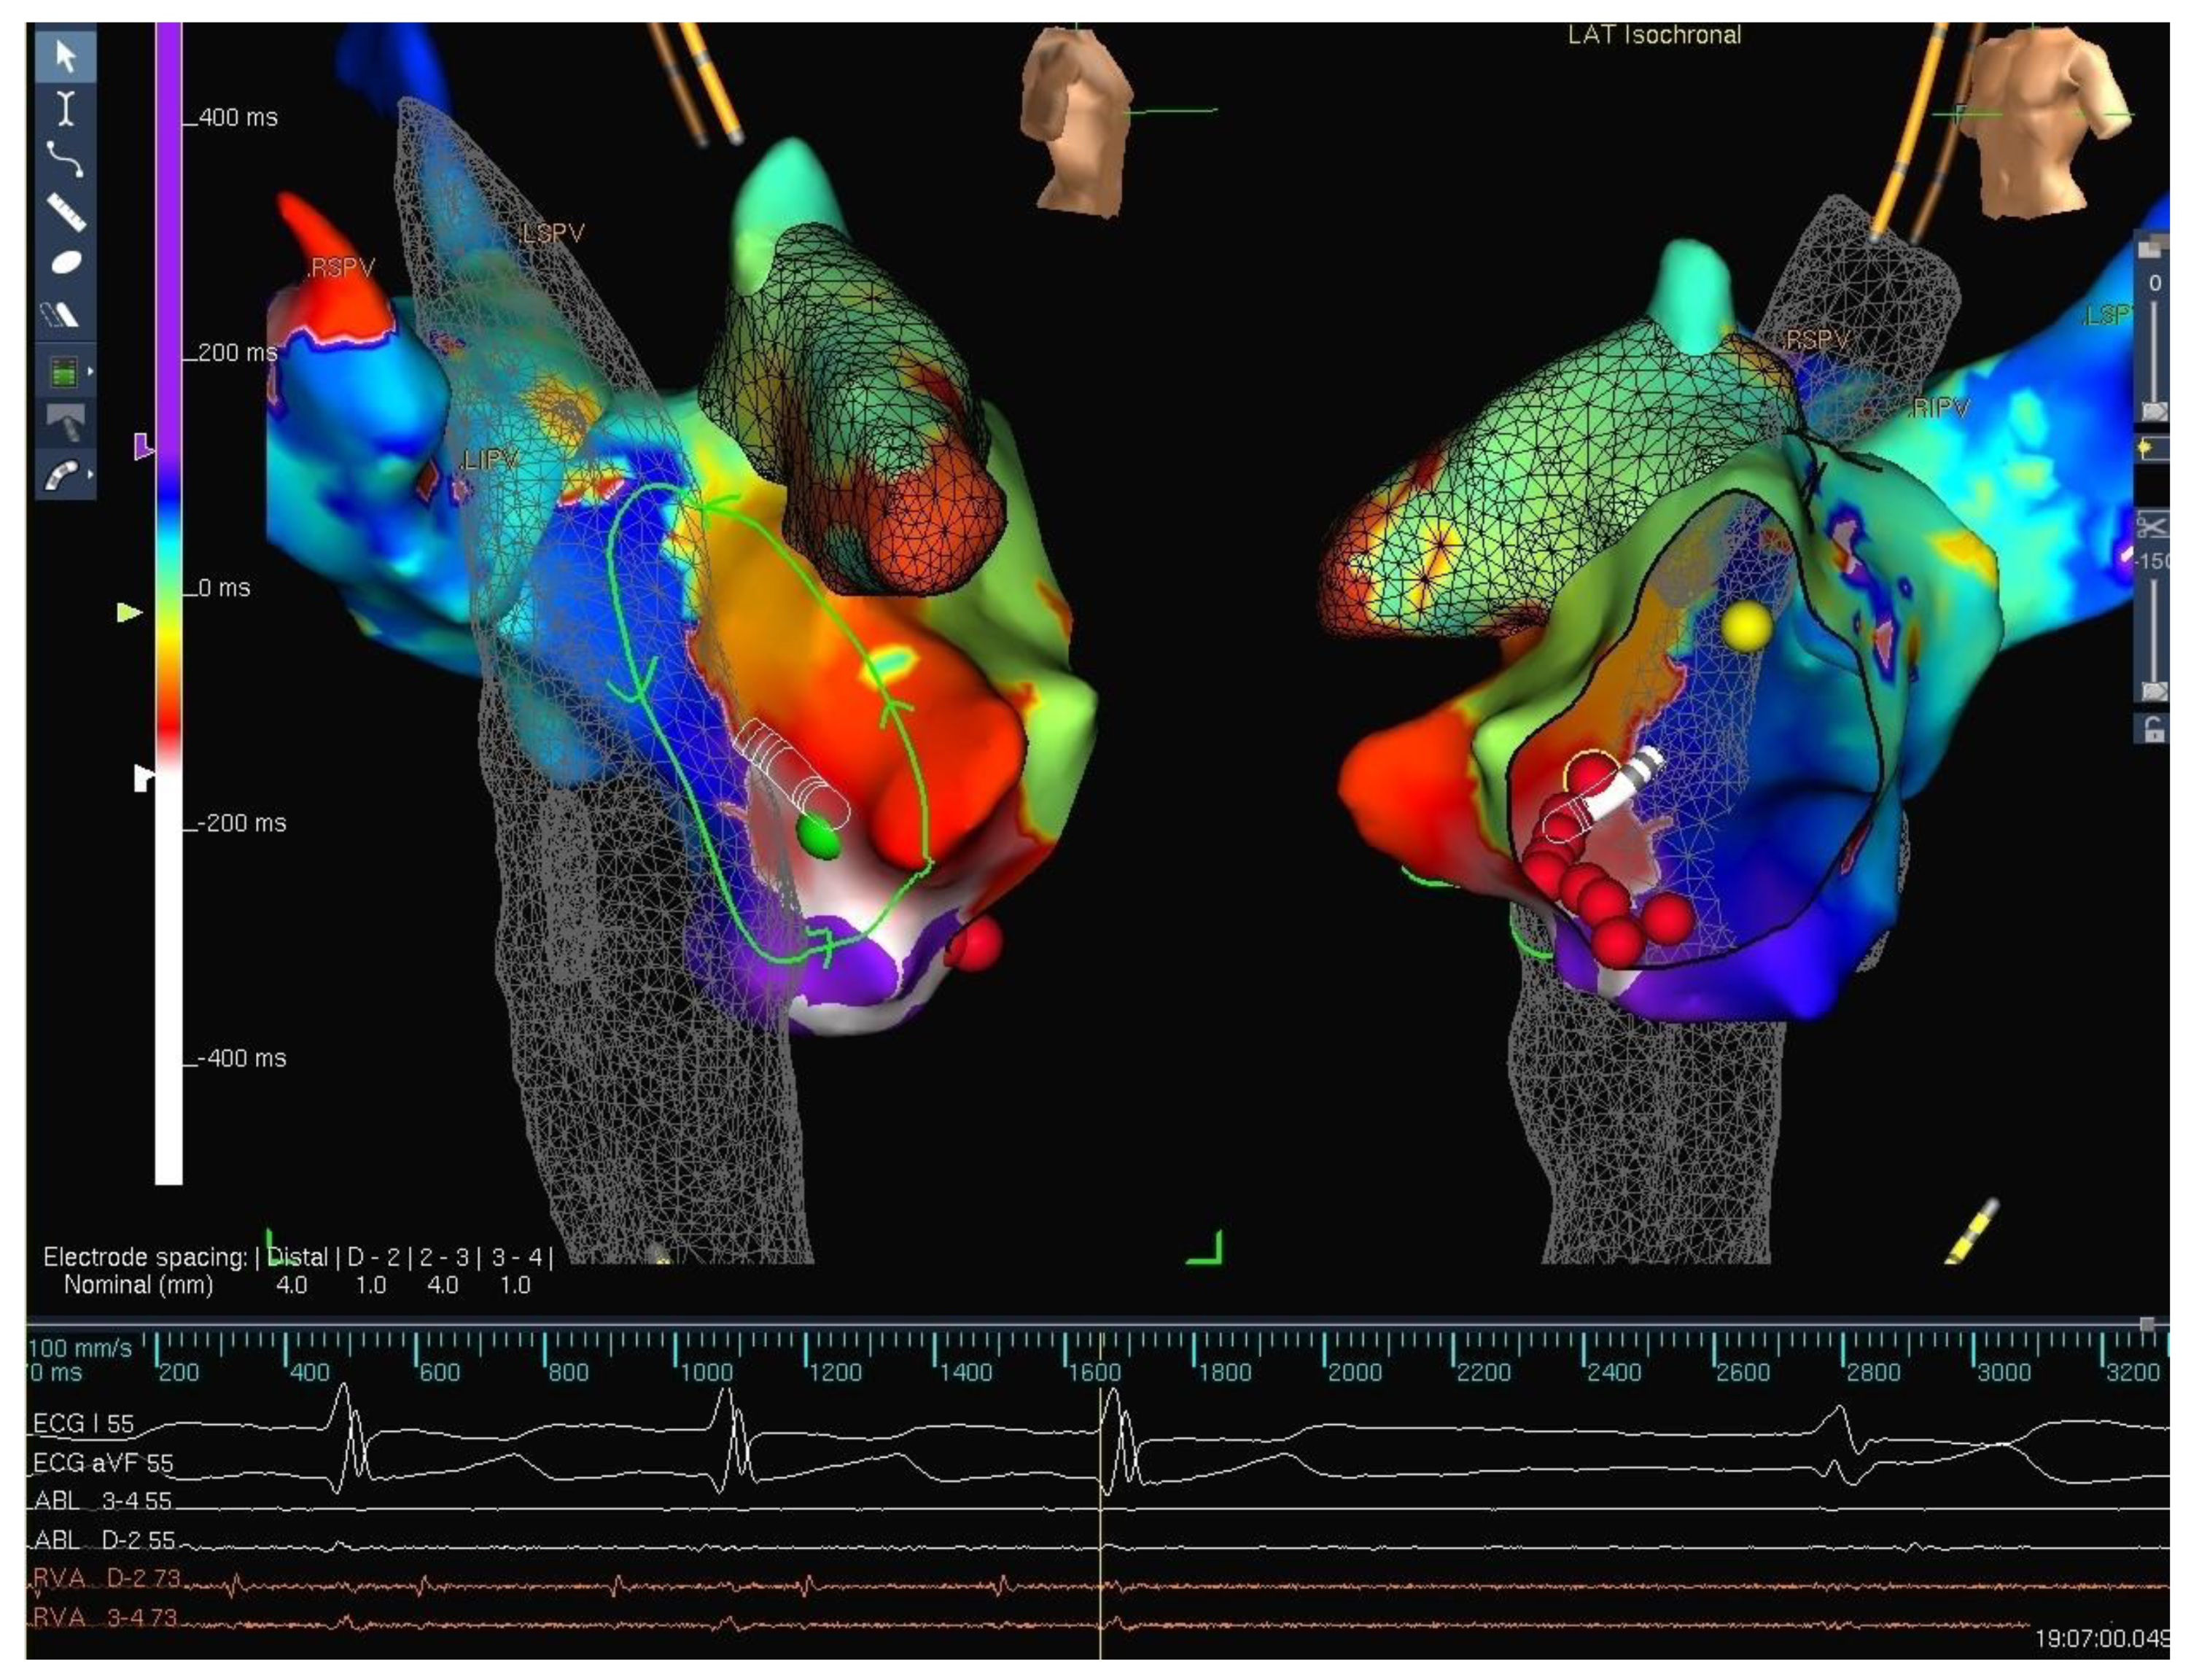

4. Strategies

5. Techniques